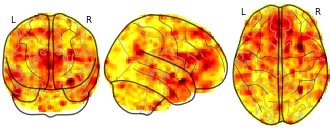

"name": "Sharbatc",

"name": "Autism",